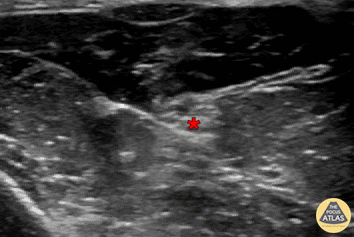

Out-of-plane median nerve block, with needle seen entering just above the nerve, with anesthetic deposited superficial to median nerve (*). Denver Health Ultrasound Fellowship